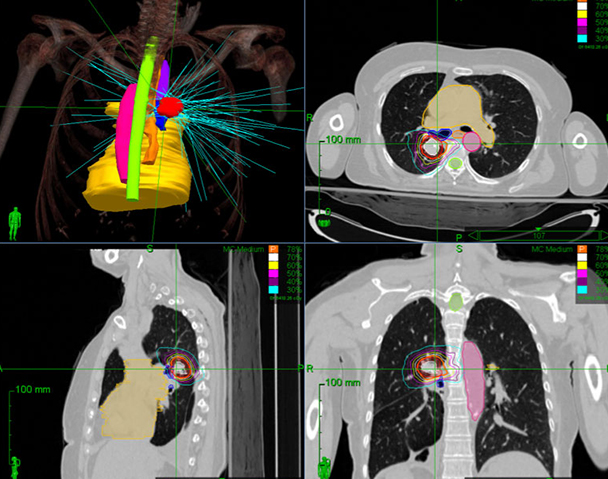

Radiation Oncologist with 7+ years of experience in Radiotherapy along with chemotherapy units. Experience in working with wide array of technologies, and expert with most advanced Linear Accelerator Radiation Modalities (Semiens, Varian Clinac ix, Elekta Versa HD, Novalis, Tomotherapy) and Eclipse version 10, Oncentra, MONACO treatment planning systems. Skilled in 3DCRT, IMRT, IGRT, RA/VMAT, SBRT & SRS.

Good experience with Cobalt and Linear Accelerator (3DCRT, IMRT, IGRT & VMAT).

Good hand on experience with SRS and SBRT.